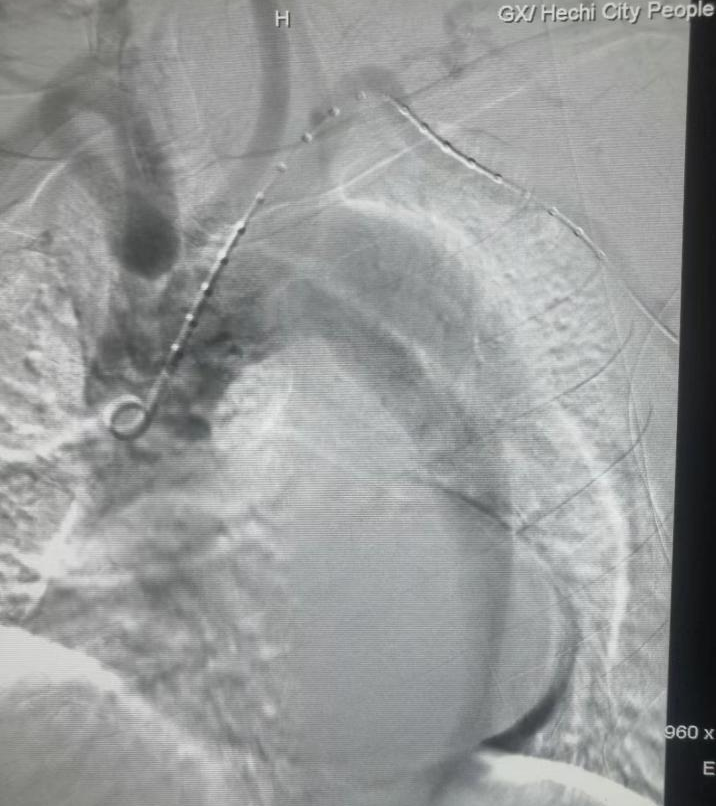

患者术中DSA影像及术后即刻造影图像